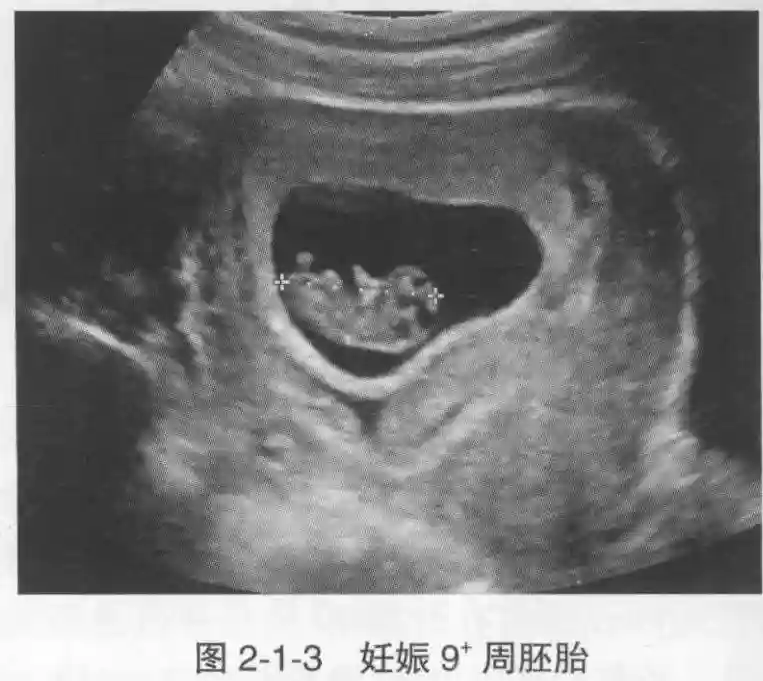

3️⃣胚胎:胚胎通常在6-7周时可以为超声显示,起初为胎芽,表现为卵黄囊一侧局部组织增厚,达到1 -2 mm 时才有可能为超声测量出来。达4-5mm时可见胎心搏动,相应孕周为6-6.5周,妊娠囊大小为13-18mm。胚芽长度≥7㎜时仍未见心管搏动,提示胚胎停止发育。胚胎的出现和妊娠囊直径的关系:妊娠囊直径> 16 mm 时,经阴道超声应显示胚胎。妊娠囊直径> 25 mm 时,经腹超声均应显示胚胎。

4️⃣胎心搏动:胎心搏动通常出现于6-6.5周,胚胎在4- 5mm就应该显示胎心搏动。